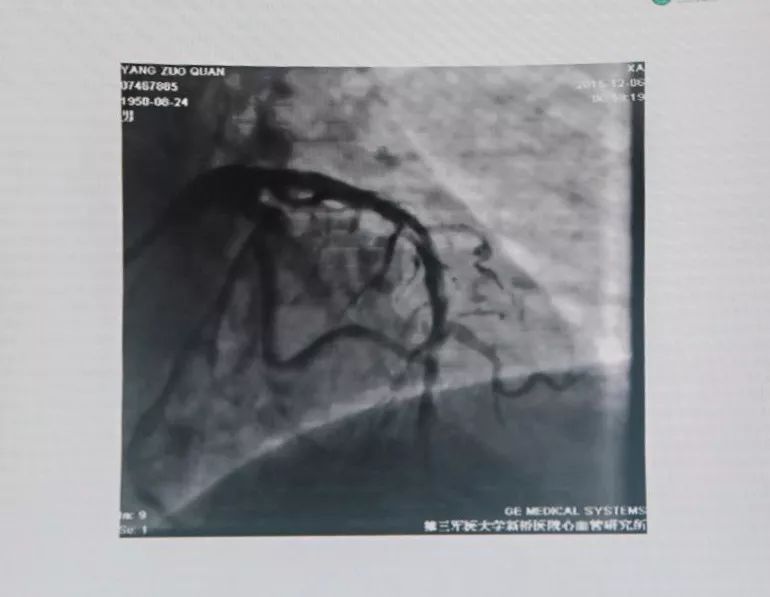

有条件者应尽快进入导管室行急诊冠状动脉造影,以多体位投照明确无夹层及支架膨胀不良。若血管完全闭塞,待球囊扩张部分血流恢复后再行造影。应尽快使导丝通过血栓病变,建议应用软头导引导丝。

支架内血栓形成可能与支架未充分贴壁有关。可用短于支架长度的高压球囊再次PTCA。若造影确认血栓形成可能与支架近或远端内膜撕裂、支架未完全覆盖病变有关,可再次置入支架,观察20 min后,若患者胸痛缓解、血压及心电监测稳定、TIMI血流III级,可视为成功。但应注意,除非有证据显示血栓形成与上述因素相关,否则不可再次置入新支架。Dutch研究发现,首次出现支架血栓的患者,再次置入新支架,发生支架血栓的风险比未置入新支架的患者增加4.2倍。